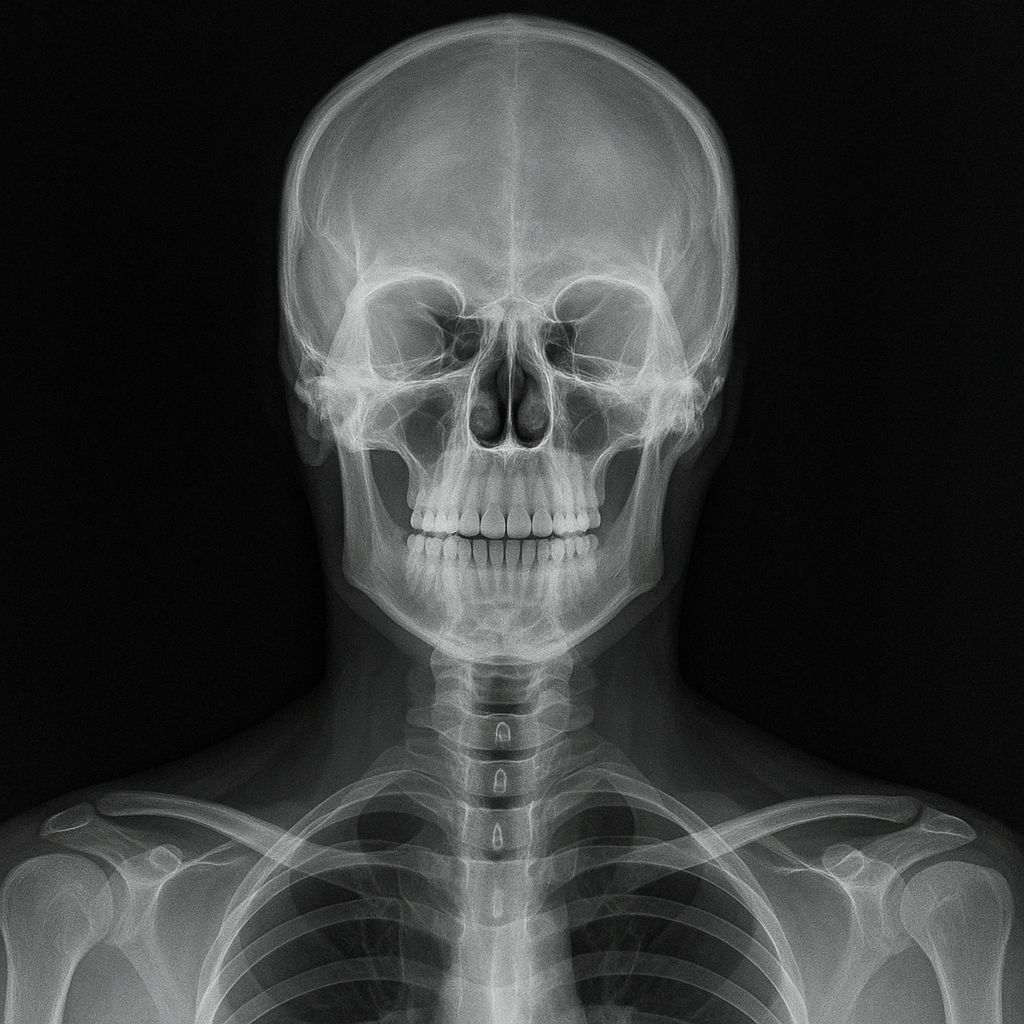

X-ray 검사는 방사선을 사용해 인체 내부를 영상화하는 기술입니다. 이때 사용되는 방사선은 ‘이온화 방사선’으로, 세포에 작용해 DNA 구조를 변형시킬 수 있는 강력한 에너지를 지니고 있습니다. 단 한 번의 X-ray 촬영이 건강에 직접적인 해를 주지는 않지만, 이 과정을 반복하게 되면 누적 방사선량이 증가하고, 인체 조직의 세포가 반복적으로 손상을 입게 됩니다. 이는 시간이 지날수록 유전자 돌연변이나 암세포 발생의 가능성을 높일 수 있습니다.

많은 사람들이 X-ray 촬영이 위험하다는 이야기를 듣고 불안해하지만, 정확한 기준과 수치를 아는 경우는 많지 않습니다. 실제로 방사선 노출은 ‘밀리시버트(mSv)’라는 단위로 측정되며, 일반적인 흉부 X-ray 1회 촬영 시 약 0.1 mSv의 방사선이 노출됩니다. 이는 우리가 자연적으로 1년간 받는 방사선량의 약 1/30 정도로, 단기적인 노출은 큰 문제가 되지 않습니다.